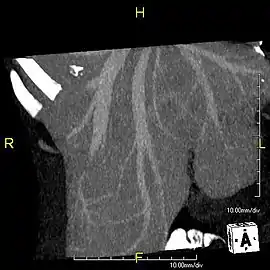

With the recent advances of noninvasive imaging, living liver donors usually have to undergo imaging examinations for liver anatomy to decide if the anatomy is feasible for donation. The evaluation is usually performed by multidetector row computed tomography (MDCT) and magnetic resonance imaging (MRI). MDCT is good in vascular anatomy and volumetry. MRI is used for biliary tree anatomy. Donors with very unusual vascular anatomy, which makes them unsuitable for donation, could be screened out to avoid unnecessary operations.

MDCT image. 3D image created by MDCT can clearly visualize the liver, measure the liver volume, and plan the dissection plane to facilitate the liver transplantation procedure.